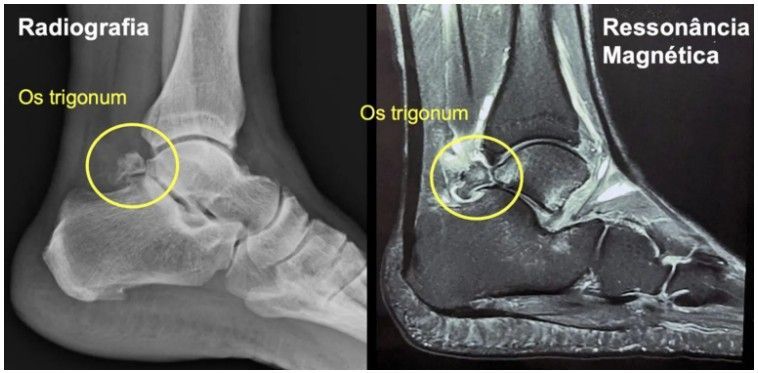

1. Radiografia (Raio-X):

- É o exame inicial e mais simples.

- Permite visualizar a presença do Osso Trígono e sua relação com o osso tálus.

- Ajuda a descartar outras causas ósseas de dor.

2. Ressonância Magnética (RM):

- Essencial para o diagnóstico da Síndrome do Impacto Posterior.

- Além de mostrar o Osso Trígono, a RM avalia os tecidos moles ao redor (ligamentos, tendões, cartilagem).

- Ela consegue identificar sinais de inflamação (edema) no próprio ossículo ou nos tecidos adjacentes, confirmando que o Osso Trígono é a causa da dor e do impacto.